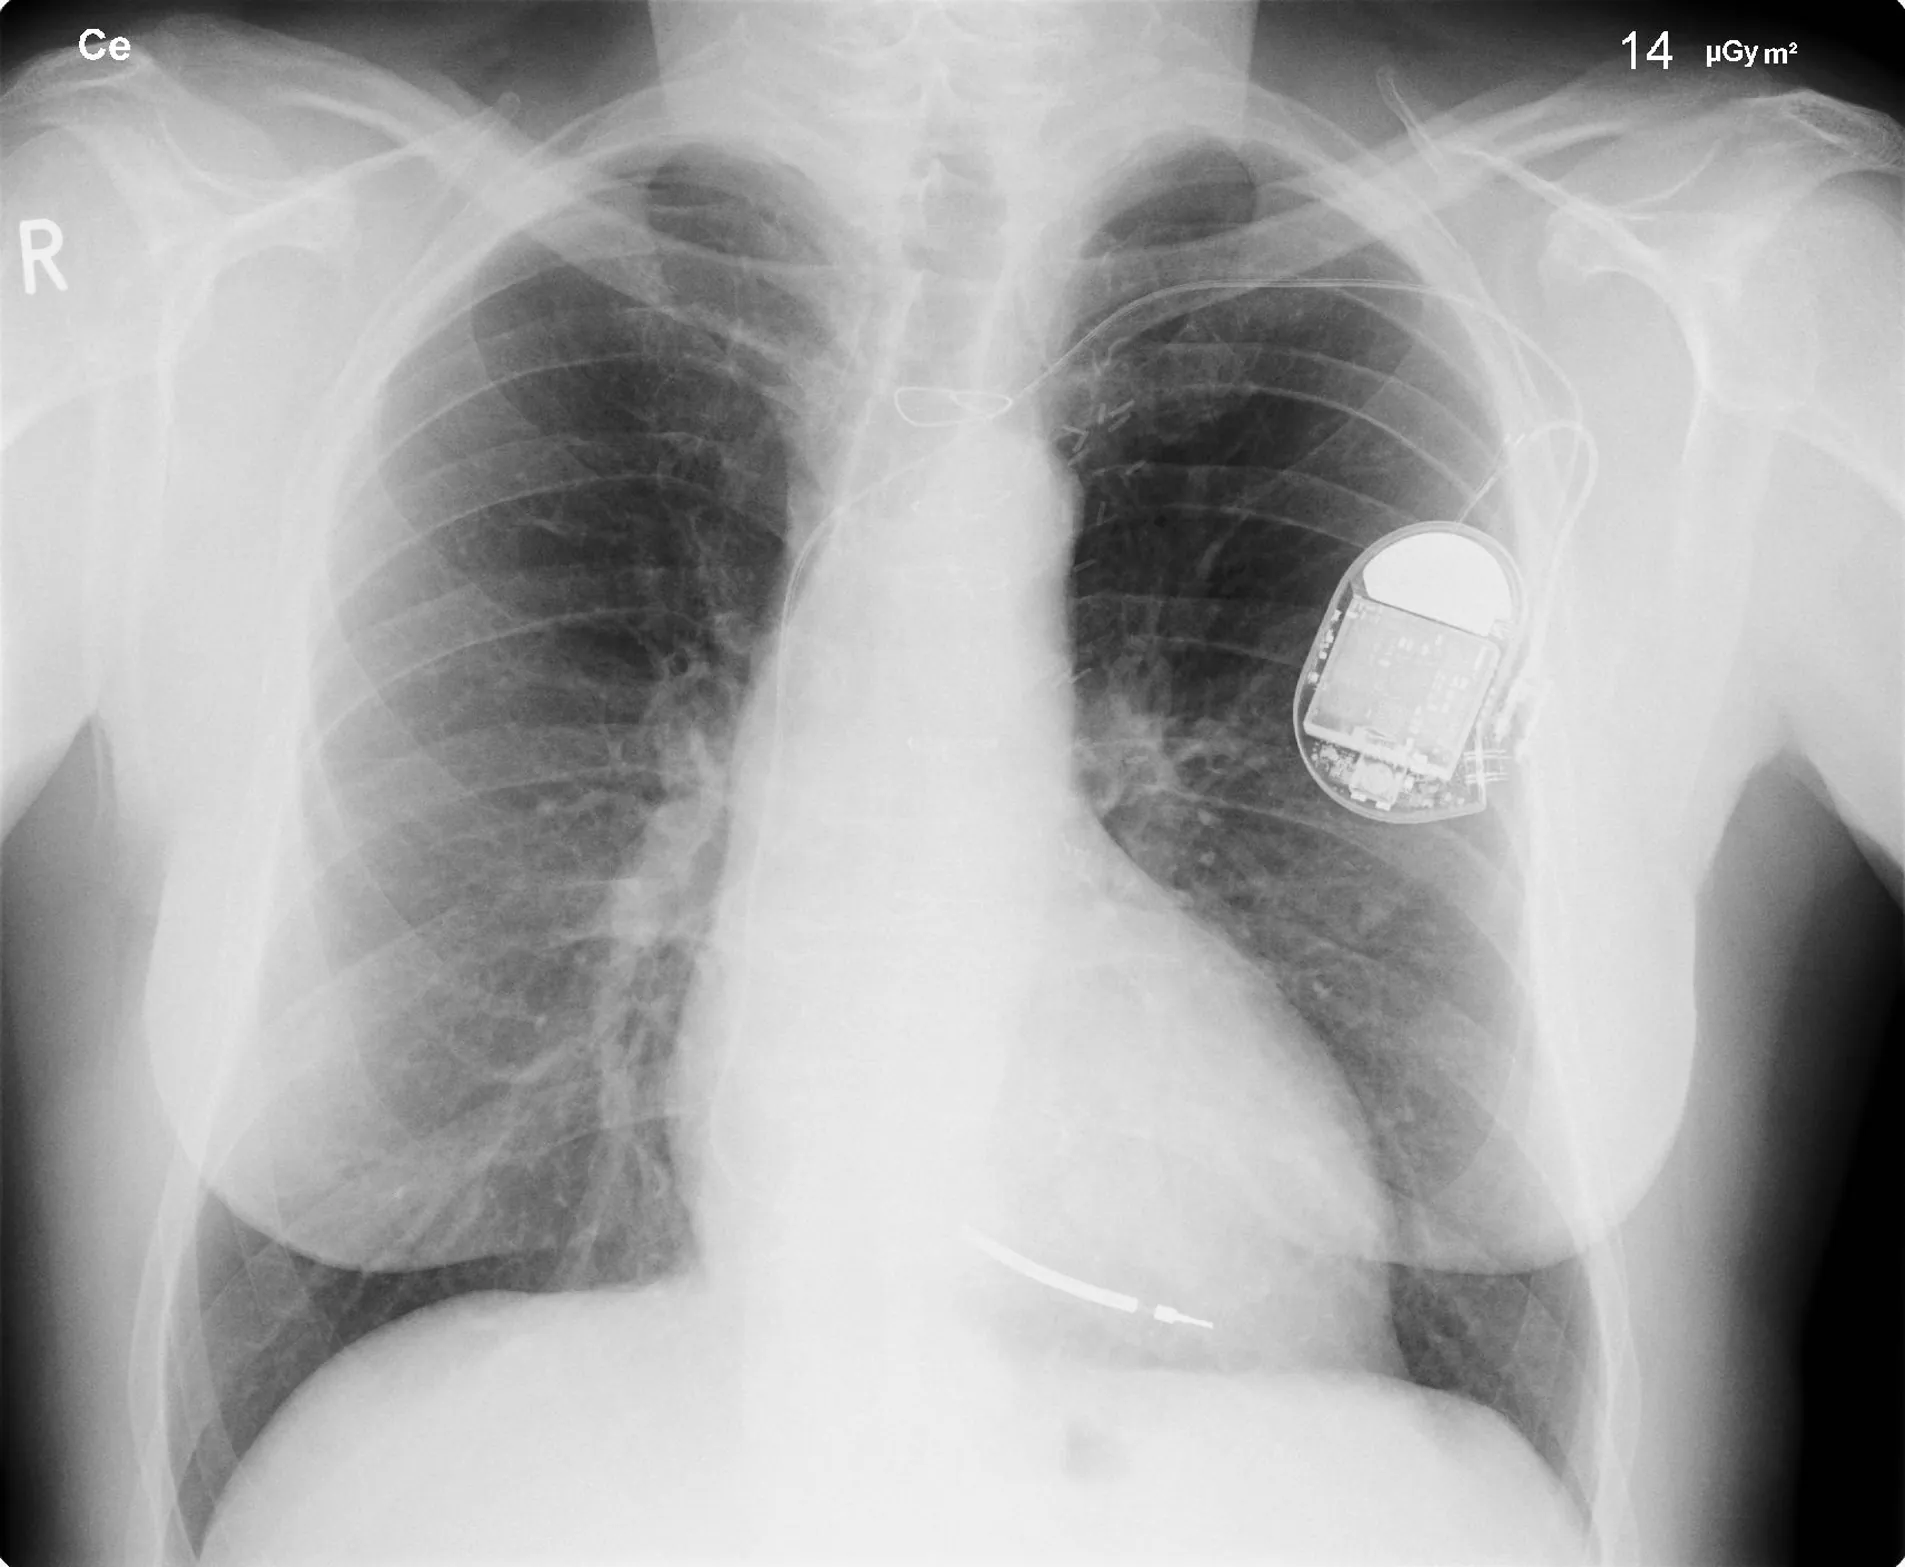

All of us can identify diagnostic uses of x-ray photons. Among these are the universal dental and medical x rays that have become an essential part of medical diagnostics. (See Figure 30.23 and Figure 30.24.) X rays are also used to inspect our luggage at airports, as shown in Figure 30.22, and for early detection of cracks in crucial aircraft components. An x ray is not only a noun meaning high-energy photon, it also is an image produced by x rays, and it has been made into a familiar verb—to be x-rayed.

An X-ray image of a person’s chest is shown, clearly showing a pacemaker in the left side.

Figure 30.23 This x-ray image of a person’s chest shows many details, including an artificial pacemaker. (credit: Sunzi99, Wikimedia Commons)

The most common x-ray images are simple shadows. Since x-ray photons have high energies, they penetrate materials that are opaque to visible light. The more energy an x-ray photon has, the more material it will penetrate. So an x-ray tube may be operated at 50.0 kV for a chest x ray, whereas it may need to be operated at 100 kV to examine a broken leg in a cast. The depth of penetration is related to the density of the material as well as to the energy of the photon. The denser the material, the fewer x-ray photons get through and the darker the shadow. Thus x rays excel at detecting breaks in bones and in imaging other physiological structures, such as some tumors, that differ in density from surrounding material. Because of their high photon energy, x rays produce significant ionization in materials and damage cells in biological organisms. Modern uses minimize exposure to the patient and eliminate exposure to others. Biological effects of x rays will be explored in the next chapter along with other types of ionizing radiation such as those produced by nuclei.